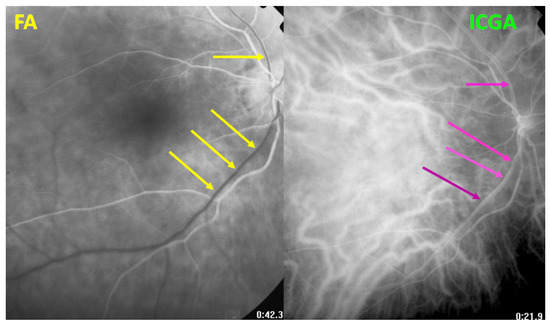

3.4.3. Indocyanine Green Angiography (ICGA) Is Essential for Choroidal Involvement and Early Diagnosis